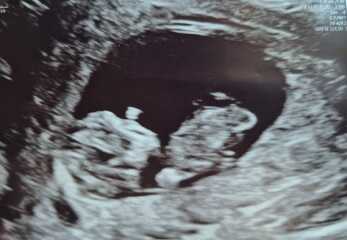

Wanttobeamommy · 31/03/2025 14:19

I don't understand nub theory so if there's anyone that does, could you have a guess at my scan please?

Nub theory guesses